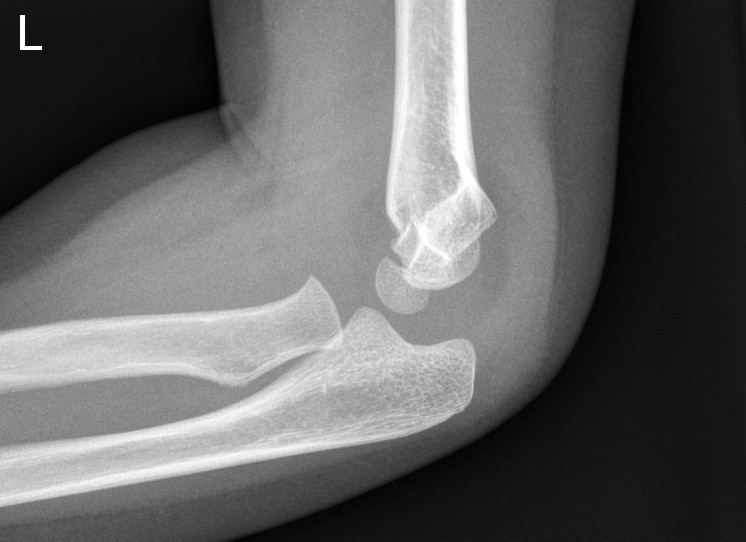

Supracondylar fracture with posterior angulation

Off-ended supracondylar fractures (Gartland Type 3)

- High risk of neurovascular compromise.

- Requires urgent Orthopaedic review and open reduction and internal fixation (ORIF) in the operating theatre.

- If applying a resting slab in ED, plaster arm in current position. Do not flex elbow.

Displaced supracondylar fracture